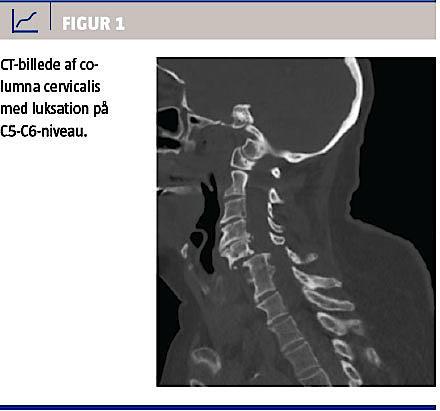

På mistanke om cervikal fraktur blev der udført akut CT af columna cervicalis. Denne viste en 8 mm anterior luksation mellem C5 og C6 med medullær påvirkning og facetledsluksation samt to mindre frakturer i hhv. C6 processus articularis superior og venstre processus transversus (Figur 1).